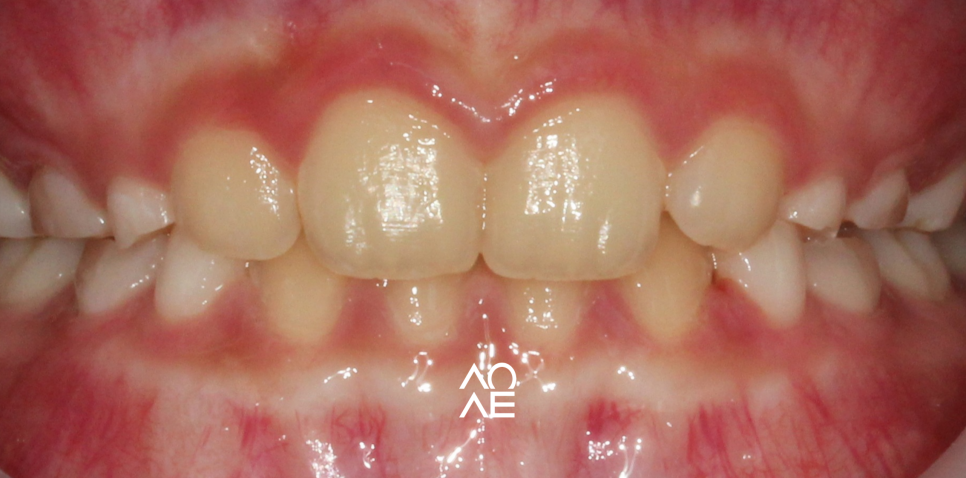

하루에 14시간 정도는

착용을 해주셔야 합니다.

수면 시간을 포함하는게 그나마

위안이 될 수 있는데요

최소 하루에 14시간 정도는 사용을

해주셔야 효과를 볼 수 있고요.

밖에서는 물론 착용하기라 쉽지 않지만

집에서는 충분히 사용을 해주세요.

특히, 수면 시간은 호르몬 분비가 되는

시간 때이기 때문에 반드시 착용해주시고요